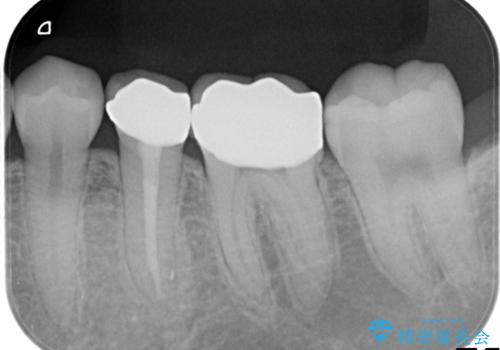

【メタルフリー】銀歯を白くしたい。オールセラミッククラウン。

- 銀歯を白くしたいと希望され来院されました。

すぐにでも白くしたいとのことで、2回目の来院で銀歯を白い仮歯に変更し喜んでいただきました。

根管治療は林先生に依頼しております。

ただ単純に白くするでけではなく拡大鏡を使用し、丁寧な処置を行なっております。